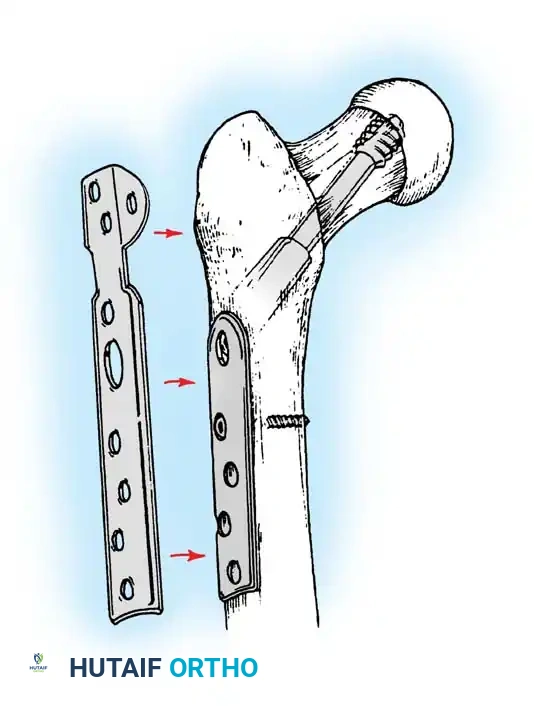

Implant Selection: SHS vs. Cephalomedullary Nail

- Sliding Hip Screw (SHS): The gold standard for stable intertrochanteric fractures (Evans Type I, AO 31-A1). The SHS allows controlled dynamic collapse along the axis of the femoral neck, compressing the fracture site and promoting primary bone healing.

4. Reaming and Lag Screw Insertion

Once the guide wire is perfectly positioned, the lateral cortex is opened, and the femoral neck is reamed over the wire.

Reaming of the femoral neck and head over the precisely placed guide wire, preparing the channel for the lag screw.

The lag screw is then inserted. It is crucial not to over-insert the screw, which can penetrate the articular cartilage, nor to under-insert it, which compromises fixation.

Final fluoroscopic evaluation confirming anatomical reduction, optimal implant placement, and restoration of the neck-shaft angle.